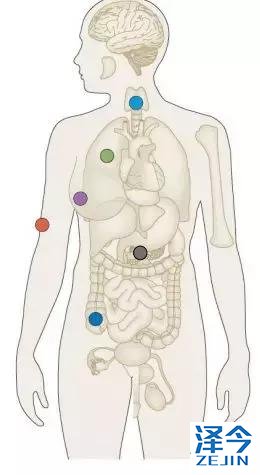

相信上面的数据和案例又让一些晚期患者看到了希望,但Rossy要提醒大家的是,LOXO-292目前没有上市,只是在临床阶段,虽然获得了突破性疗法认证,距离上市也还有不短的试验。目前,只有通过去国外参加临床试验才能用到,但Rossy建议大家先接受正规的治疗,在没有更好治疗方案的情况下可以考虑,另外,由于这款药物是针对RET基因的,所以大家做过多基因检测的患者,可以先看看是否有这个RET基因突变或者融合。没做过的可以尝试进行检测。据了解,在非小细胞肺癌里面,大约1%-2%的患者有RET基因融合,在甲状腺髓样癌中超过60%的患者有RET基因突变,在乳头状甲状腺癌中10%的患者有RET基因融合。